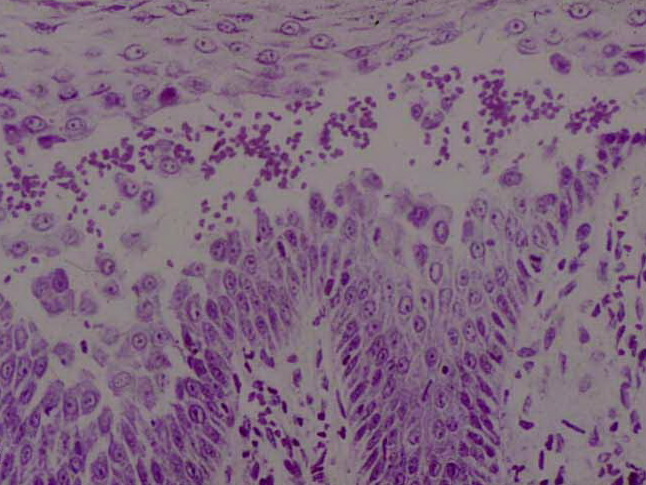

Atlas of skin histopathology

Histiocytosis X =x كثرة المنسجات